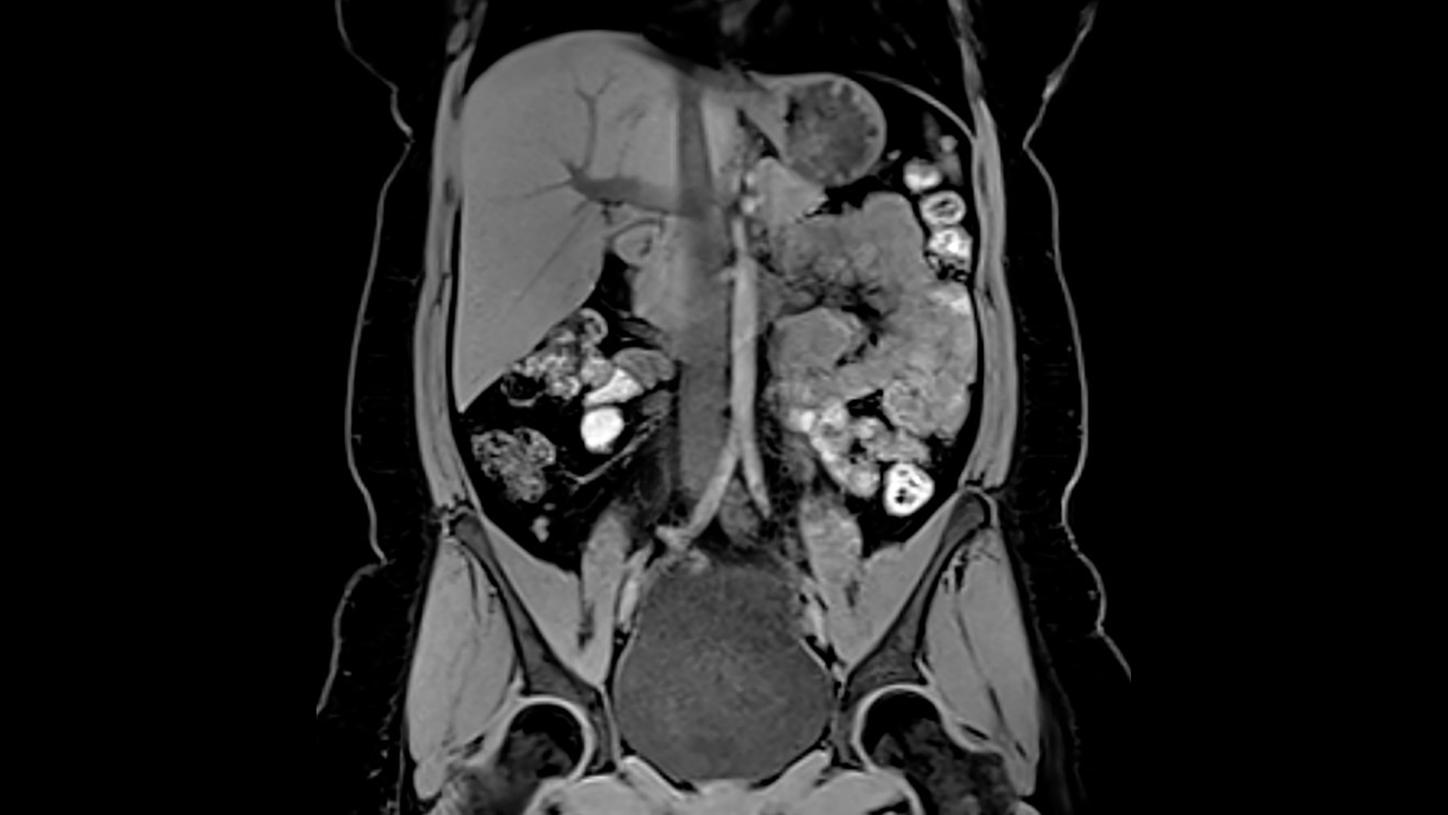

Key investigation areas for MRI are soft tissue areas like brain, abdomen, vessels, ligaments, cartilages or muscles.

Fig.2: Courtesy of Siemens Healthcare GmbH, Germany